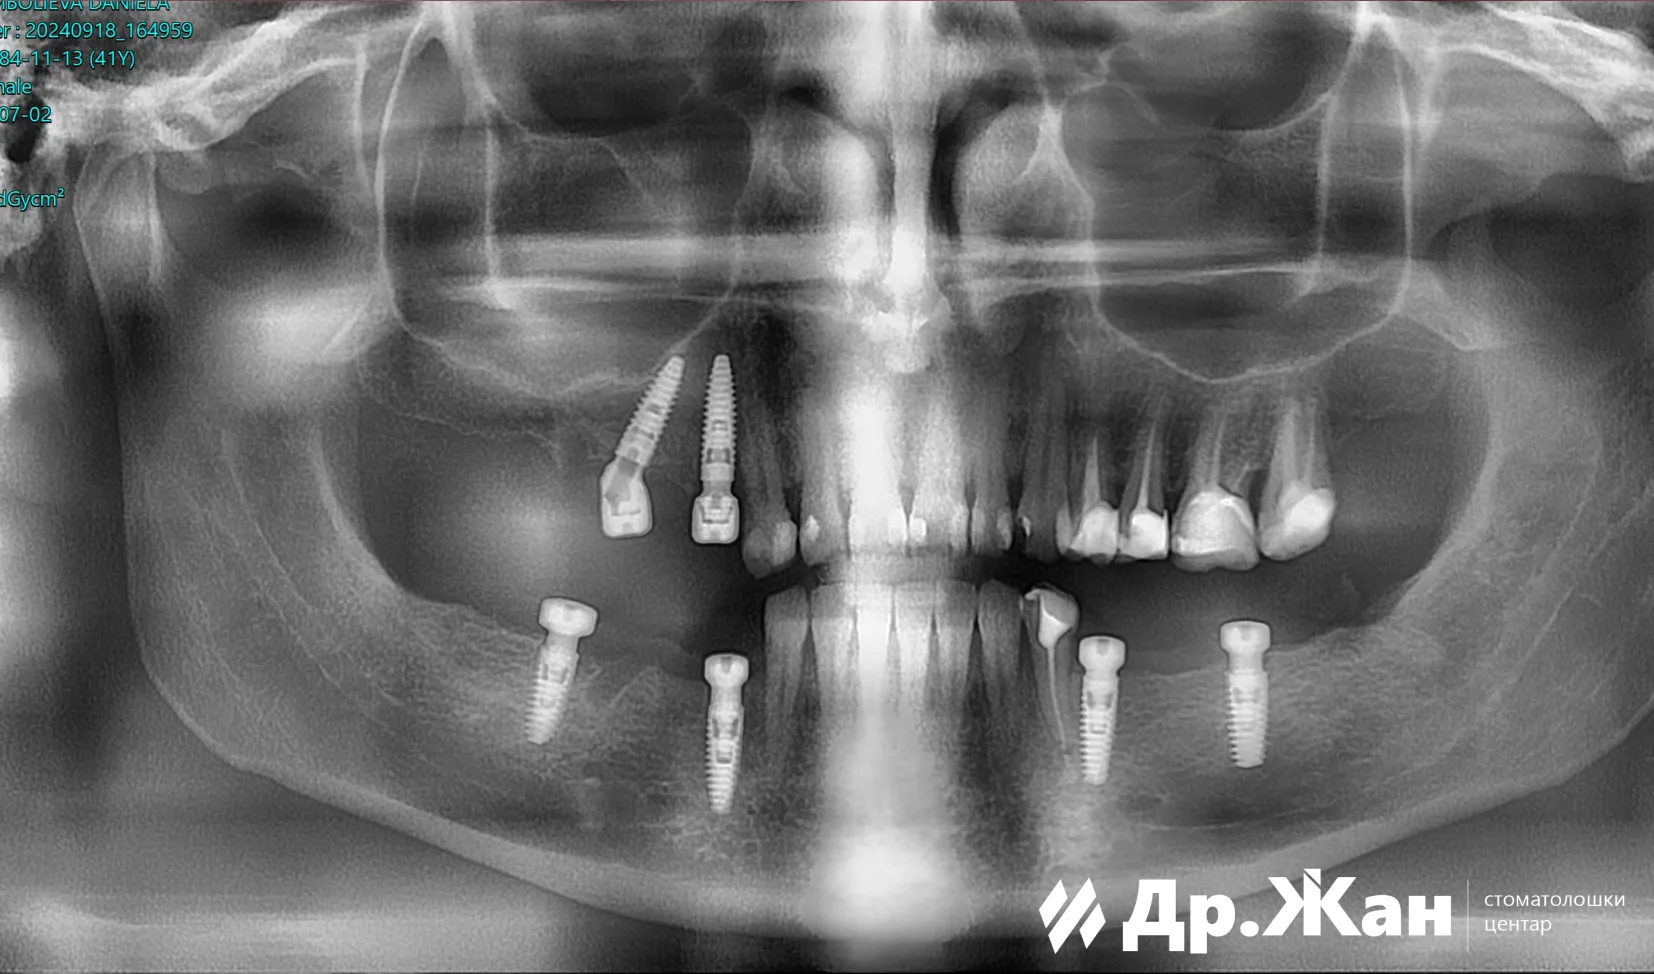

По прегледот и анализата, планот за терапија беше целосна реконструкција на устата со забни импланти и циркониумски коронки и мостови. Преостанатите корени беа извадени и шест забни импланти беа поставени со помош на хируршки водич и дигитален работен тек.

По периодот на заздравување од 6 месеци, забите беа подготвени и беше поставена прототип насмевка со привремени заби. По анализата на прототип насмевката, ги направивме сите потребни промени за да ѝ обезбедиме на оваа пациентка оваа нова прекрасна насмевка со циркониумски коронки и мостови преку забните импланти. Сето ова беше направено со дигитален работен тек.